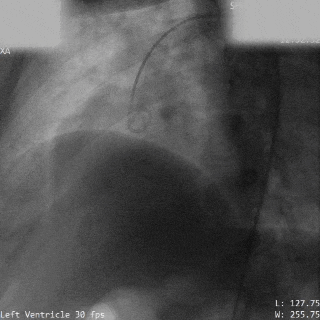

术前造影

主动脉瓣上造影,破口约5mm

释放前瓣上造影

分流明显减少